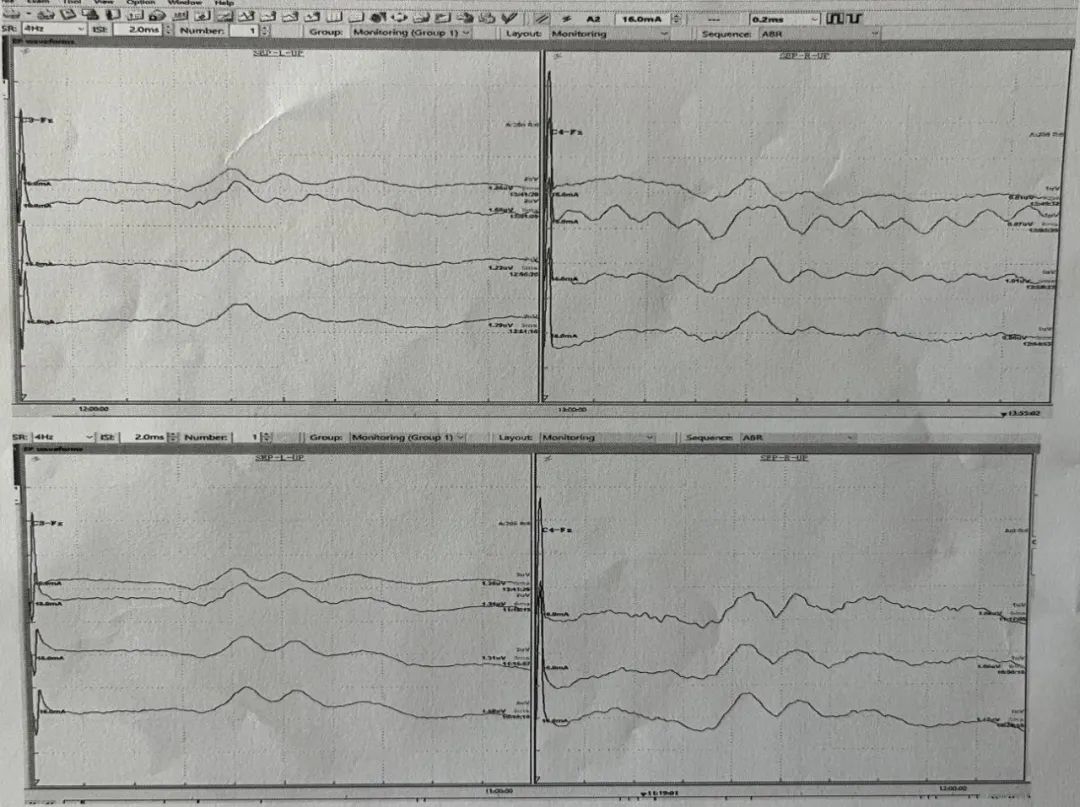

术中脑功能监测 —— 脑电图+诱发电位

脑功能监测能够在手术过程中实时评估患者的脑功能状态,防止脑功能发生不可逆的损害,及时对神经损伤风险进行预警,从而减少术后并发症的发生。